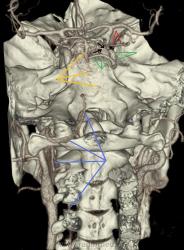

Наблюдение Nela.

Персистирующая примитивная тройничная артерия.

Мужчина 63 лет с жалобами на опущение верхнего века справа. Направлен на КТ-ангиографию для исключения аневризмы в области сифона правой внутренней сонной артерии.

При КТА отмечается гипоплазия вертебральных артерий, больше выраженная справа. Основная артерия на большем протяжении не развита, дистальная часть ее питается из расширенной примитивной тройничной артерии, отходящей от проксимальных отделов сифона правой внутренней сонной артерии. Кроме этого правая задняя мозговая артерия отходит от супраклиноидного отдела внутренней сонной артерии – задняя трифуркация. Слева отсутствует задняя соединительная артерия.

Таким образом кровоснабжение вертебро-базиллярного бассейна осуществляется из правой внутренней сонной артерии.

Голубые стрелки – вертебральные артерии.

Красные – задние мозговые.

Зеленые – тройничная артерия.

Желтые – основная артерия.

Черные – сифон внутренней сонной.